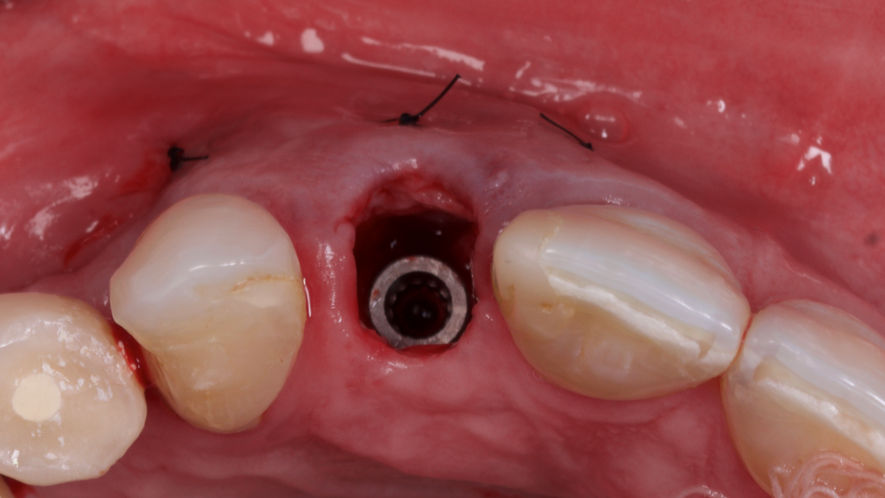

Este trabalho tem como objetivo relatar um caso clínico de exodontia minimamente invasiva de um incisivo lateral superior com fratura radicular, realizando implante imediato em alvéolo pós-extração, enxerto de tecido conjuntivo subepitelial e osso bovino liofilizado para preenchimento de GAP, prontamente à instalação de pilar reto e provisório imediato.